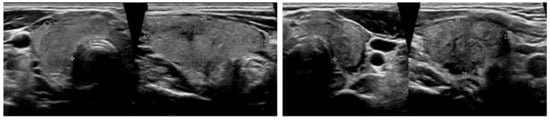

It was noted in the report that the finding could be compatible with thyroiditis and that the patient was promptly presented at our Out-Patients Department of Thyroid Diseases, where an ultrasound of the neck was performed. It showed an enlarged thyroid gland with heterogeneous echostructure. Both lobes had hypoechoic areas with ill-defined margins. There was one nodule seen in the right thyroid lobe, measuring up to 1 cm (Figure 2). Color flow Doppler showed reduced blood flow in both lobes.

Figure 2.

Ultrasound images at the time of the diagnosis of SAT. The total volume of the thyroid gland was about 18 mL (right lobe 10.1 mL and left lobe 7.2 mL) with heterogeneous echotexture and hypoechoic areas with ill-defined margins. SAT, subacute thyroiditis.

Thyroid gray-scale ultrasonography combined with color Doppler is a very effective, validated, and sensitive tool in diagnosing and monitoring thyroid disorders. Park et al. suggested that heterogeneous diffusely or focally ill-defined elongated hypoechoic areas without flow are typical findings of SAT [10]. Even if the inflammation process involves the entire thyroid, the patients with SAT could present an asymmetric enlargement of the gland. A further validated imaging modality in patients with thyroid diseases is the [99mTc]Tc-pertechnetate scintigraphy. In the acute phase of SAT, a [99mTc]Tc-pertechnetate scan shows markedly reduced uptake in the entire gland [11]. Thyroid gray-scale ultrasonography and [99mTc]Tc-pertechnetate scintigraphy are generally performed promptly in patients with thyrotoxicosis and typical neck pain, because of suspected thyroiditis. Generally, both these imaging investigations in association with a thyrotoxicosis on the blood tests could allow a timely diagnosis of SAT, without resorting to 2-[18F]FDG PET/CT, a more expensive examination with a higher radiation burden. Nevertheless, our patients presented only a previous clinical history of FUO, without the typical clinical and biochemical features of a thyroiditis. Precisely, in patients with light or absent neck pain, with only elevated hsCRP on laboratory samples, and with a clinical history of FUO or IUO, 2-[18F]FDG PET/CT may be helpful for the differential diagnosis of SAT, according with our case and with those reported by Yoshida et al. and Lambert et al. [12,13].

Yen et al. described a case of localized SAT in a patient, which underwent 2-[18F]FDG PET/CT. A focal, intensely hypermetabolic thyroid lesion was reported, and the probability of malignancy was also considered [9]. Moreover, localized hypoechoic lesions on ultrasound and asymmetry of the thyroid are also common findings for a thyroid carcinoma. Nevertheless, the common forms of thyroid carcinomas (papillary and medullary thyroid carcinomas) are usually hypervascular. Zacharia et al. explained that, in this controversial case, a fine-needle aspiration biopsy is necessary to confirm the diagnosis [14].